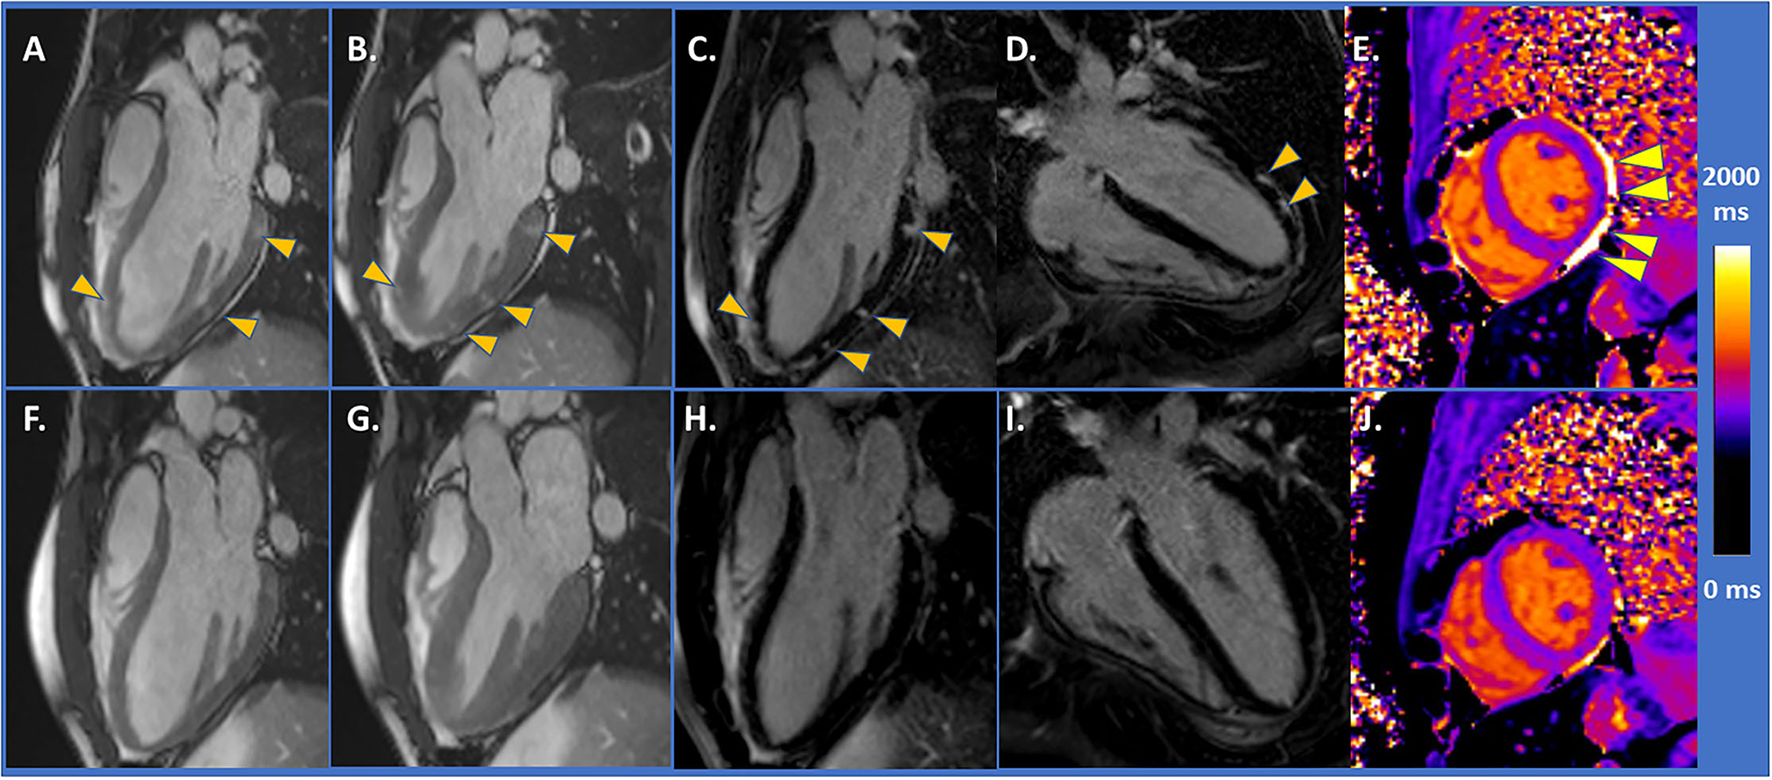

The CMR imaging showed acute myocarditis, and mildly impaired LV-function (EF = 49%) [Figures 1A,B, arrowheads depict areas of higher contrast-to-noise ratio in diastolic (A) and systolic (B) SSFP images, performed prior to gadolinium administration, compatible with myocardial oedema]. Abundant subepicardial LGE was detected [arrowheads in Figures 1C,D], whereas native T1 value, measured in the mid-ventricular septum, was within normal range (T1 = 1,000 ms, Figure 1E, arrowheads depict small pericardial effusion) (T1 and T2 images and values are provided in Supplementary Figure 2). Heart failure treatment with bisoprolol 2.5 mg per day was initiated, and the patient exhibited prompt clinical recovery. Control CMR after 3 months showed full functional recovery with an EF of 62% (Figures 1F,G) and disappearance of LGE (Figures 1H,I). T1 value was 990 ms (Figure 1J).

Figure 1

(A,B) CMR demonstrated mildly impaired LV-function and areas of higher contrast-to-noise ratio (arrowheads) with SSFP images. (C,D) With LGE images, abundant subepicardial LGE was detected (arrowheads). (E) Native T1 value was within normal range (T1 = 1,000 ms, arrowheads depicting small pericardial effusion). (F,G) Control CMR after 3 months showing full functional recovery and disappearance of LGE in (H,I). (J) T1 value of 990 ms.